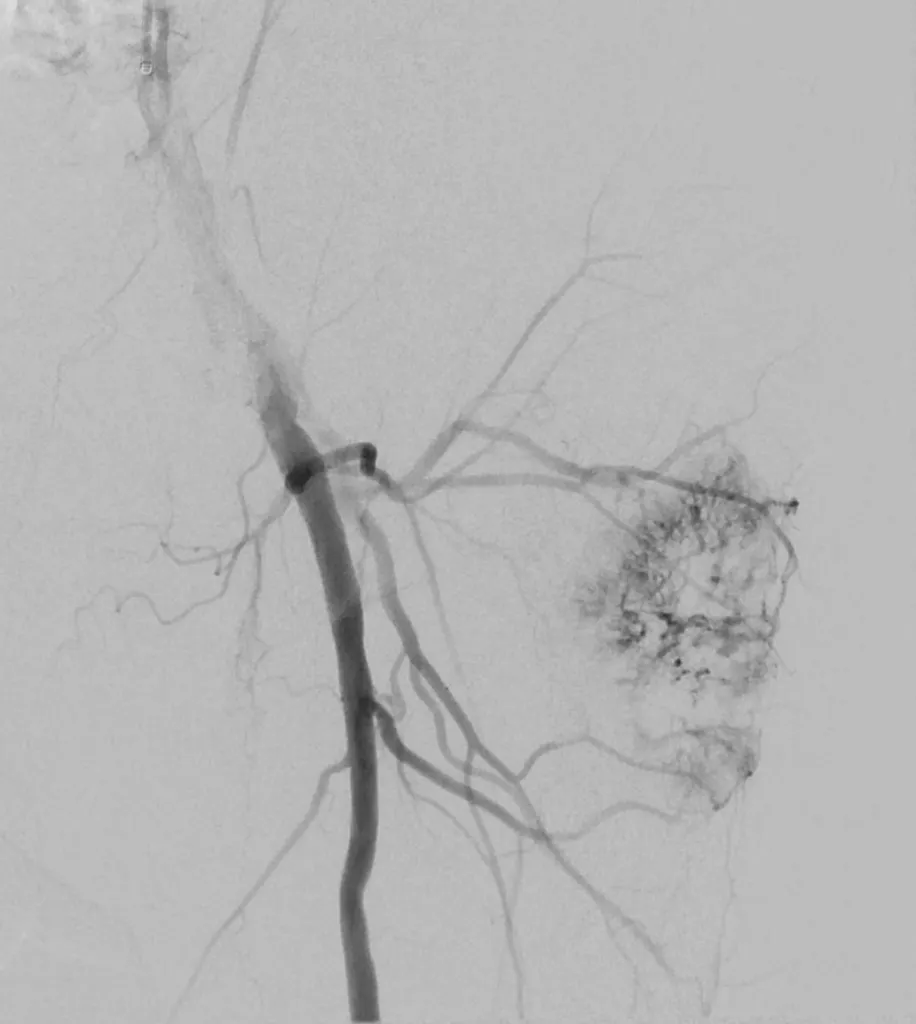

65 year old with a left femoral renal metastasis lesion. Angiograms showing vascularity of the lesion. The two annotated images show the tortuosity of the vessel supplying the lesion. The dotted orange coloured line shows the path of the vessel. It was not possible to cannulate this artery with conventional microcatheters.